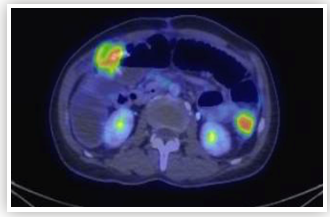

Cytoreductive Surgery and Hyperthermic Intraperitoneal Chemotherapy: Unconventional Indications

Chin Jin Seo, Grace Hwei Ching Tan, Kee Chee Soo and Melissa Ching ChingTeo. 1(1): 12-20.